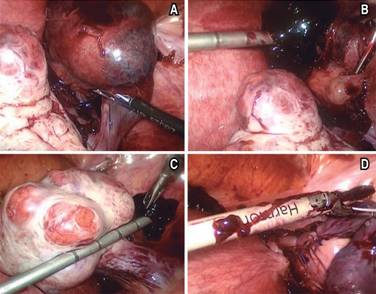

Se presentó al Servicio de Urgencias con los siguientes signos vitales: FC, 80 lpm; FR, 21 rpm; TA, 120/80; T, 37 oC; refería cuadro de dolor abdominal de aparición súbita con aproximadamente siete horas de evolución, constante, en la fosa iliaca derecha (FID), EVA 7/10, irradiado a la región lumbar ipsilateral, vómito en una ocasión de contenido gástrico, sin fiebre, acompañado de náusea y sangrado transvaginal de aproximadamente 15 cm3; negó ingesta previa de medicamentos, así como la presencia de exacerbantes y atenuantes. A la exploración, se encontró abdomen globoso a expensas de panículo adiposo, peristalsis presente, disminuida en la FID; abdomen blando, resistencia muscular voluntaria, doloroso a la palpación superficial, media y profunda en la FID; hiperbaralgesia e hiperestesia dudosas de predominio en la FID; no se palpó crecimiento uterino; dolor en punto de McBurney (+), VonBlumberg (+), Rovsing (-), talopercusión (+). Laboratorios de ingreso, con hemoglobina de 13.2, hematocrito de 38, leucocitos de 26.9, segmentado 95, BUN 10.2, urea 22.1, creatinina 0.58. El USG ginecológico reportó útero gestante de 12.0 × 8.2 × 7.4 cm en sus ejes longitudinal, AP y transversal. En la cavidad endometrial se observaron dos sacos gestacionales de localización normal y apariencia viable, compatibles con embarazo gemelar intrauterino; fondo de saco de Douglas con líquido libre; fosa iliaca derecha en topografía del ciego, se observó asa de paredes levemente engrosadas y peristalsis ausente, líquido libre alrededor; no se pudo descartar proceso inflamatorio apendicular (Figura 1). Se programó apendicectomía laparoscópica; se halló hemoperitoneo de 250 cm3, salpinge derecha aumentada de tamaño, rota y con sangrado activo compatible con embarazo ectópico roto, coágulo organizado en la FID; útero grávido aumentado de tamaño, anexo izquierdo normal, ovario derecho con cuerpo lúteo. Se realizó salpingectomía derecha, evacuación de hemoperitoneo y lavado de cavidad; se colocó drenaje tipo Blacke 19 French (Figura 2); postoperatorio con diagnóstico de embarazo heterotópico roto derecho (Figura 3). La paciente pasó compensada a la Unidad de Cuidado Postoperatorio. Al día siguiente, drenaje con gasto de 85 cm3 serohemático; se realizó un USG obstétrico que reportó vitalidad y viabilidad de los productos fetales intrauterinos (Figura 4). Cuarenta y ocho horas posteriores al procedimiento quirúrgico, se retiró el drenaje y fue dada de alta por los Servicios de Ginecología y Cirugía General. El nacimiento de dos productos, uno del sexo masculino y otro femenino, se llevó a cabo a las 35 SDG mediante cesárea; la indicación de la misma fue preeclampsia desarrollada durante el embarazo. No se presentaron complicaciones durante el procedimiento.

Figura 2: (A) Tuba uterina derecha y componente ectópico del embarazo. (B) Sitio de ruptura del componente ectópico. Se aprecia útero aumentado de tamaño y ovario derecho. (C) Ovario derecho sin compromiso. (D) Corte de la tuba uterina y componente ectópico con bisturí Harmónico®.